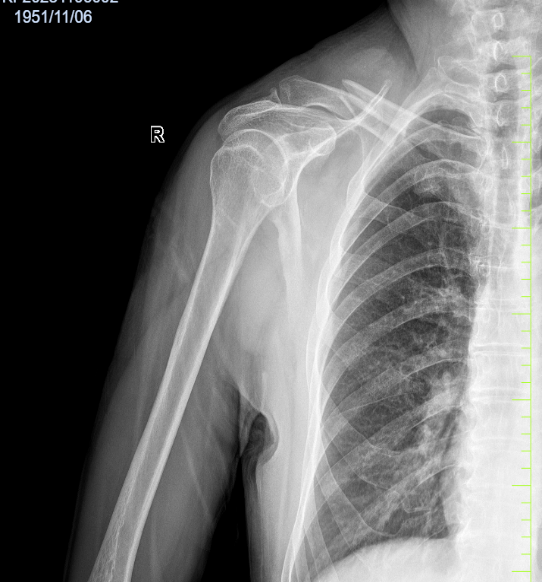

病例六:患者,男,71岁,因“摔伤致右肩部疼痛伴活动受限1小时余”入院。诊断:右锁骨骨折;行右锁骨骨折切开复位内固定术;手术顺利,术后恢复良好,顺利出院。

右锁骨骨折 术前X线片 右锁骨骨折 术前三维CT

右锁骨骨折 术后X线片